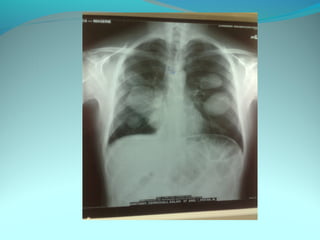

Opacité triangulaire a base cardiaque a sommet

axillaire dense et homogène

Par ailleurs on note

Une opacité plus dense que celle arrondie de 3cm de

diam hilaire gauche ;une surélévation de la coupole

diaphragmatique gauche é poche a aire gastrique

DIAGNOSTIC :

ADP hilaire gauche avec trouble de ventilation

Surelevation de la coupole G et de la poche gastrique

avec de clarté le médiastin

DIAGNOSTIC:

Hernie diaphragmatique paralysie du diaphragme